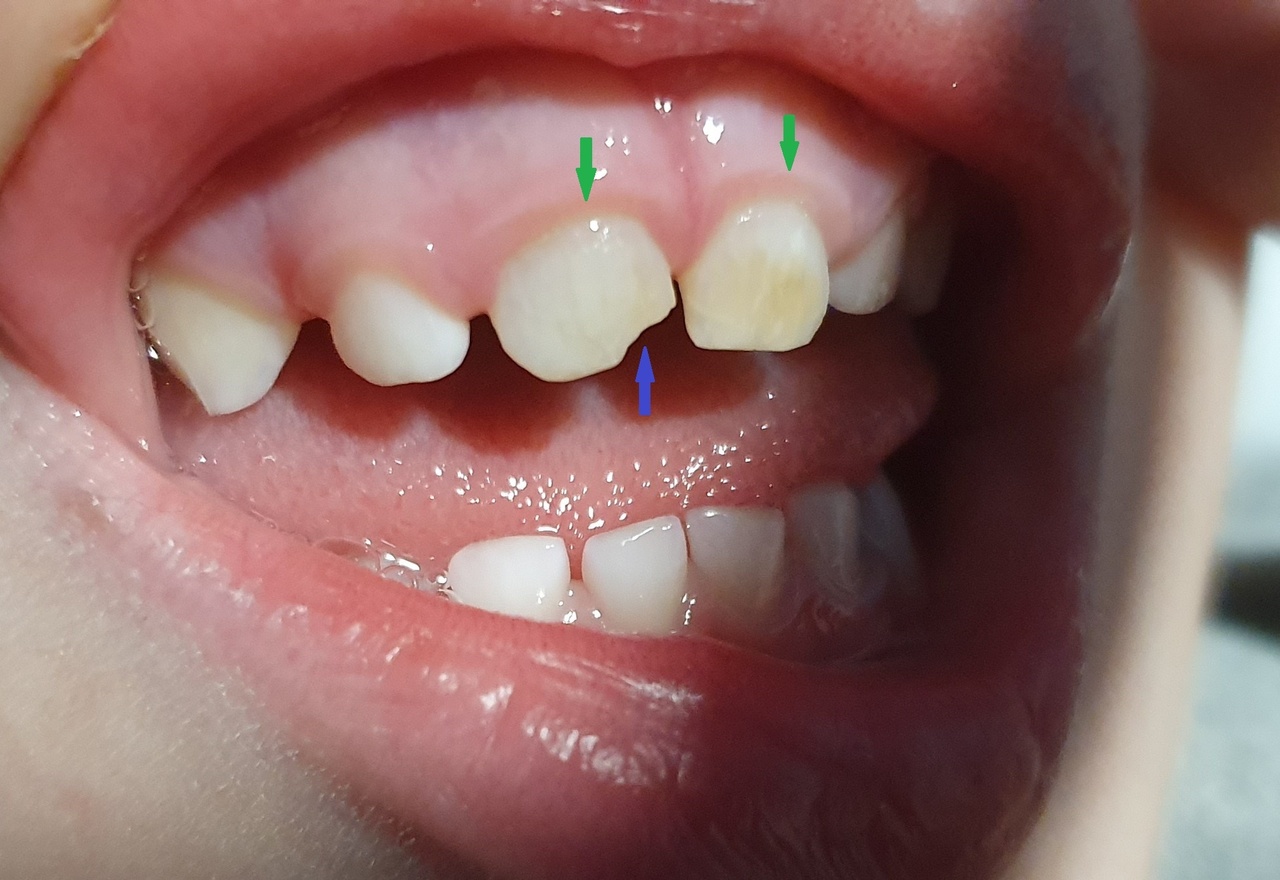

Gabriel, 3 ans, se plaint de douleurs au niveau des gencives depuis quelques jours.

L’examen clinique révèle une hypertrophie gingivale (figure, flèches vertes) et une incisive partiellement cassée (figure, flèche bleue).

À l’interrogatoire, la mère explique que cette anomalie est apparue il y a quelques mois. Elle révèle également que son enfant refuse les soins dentaires.